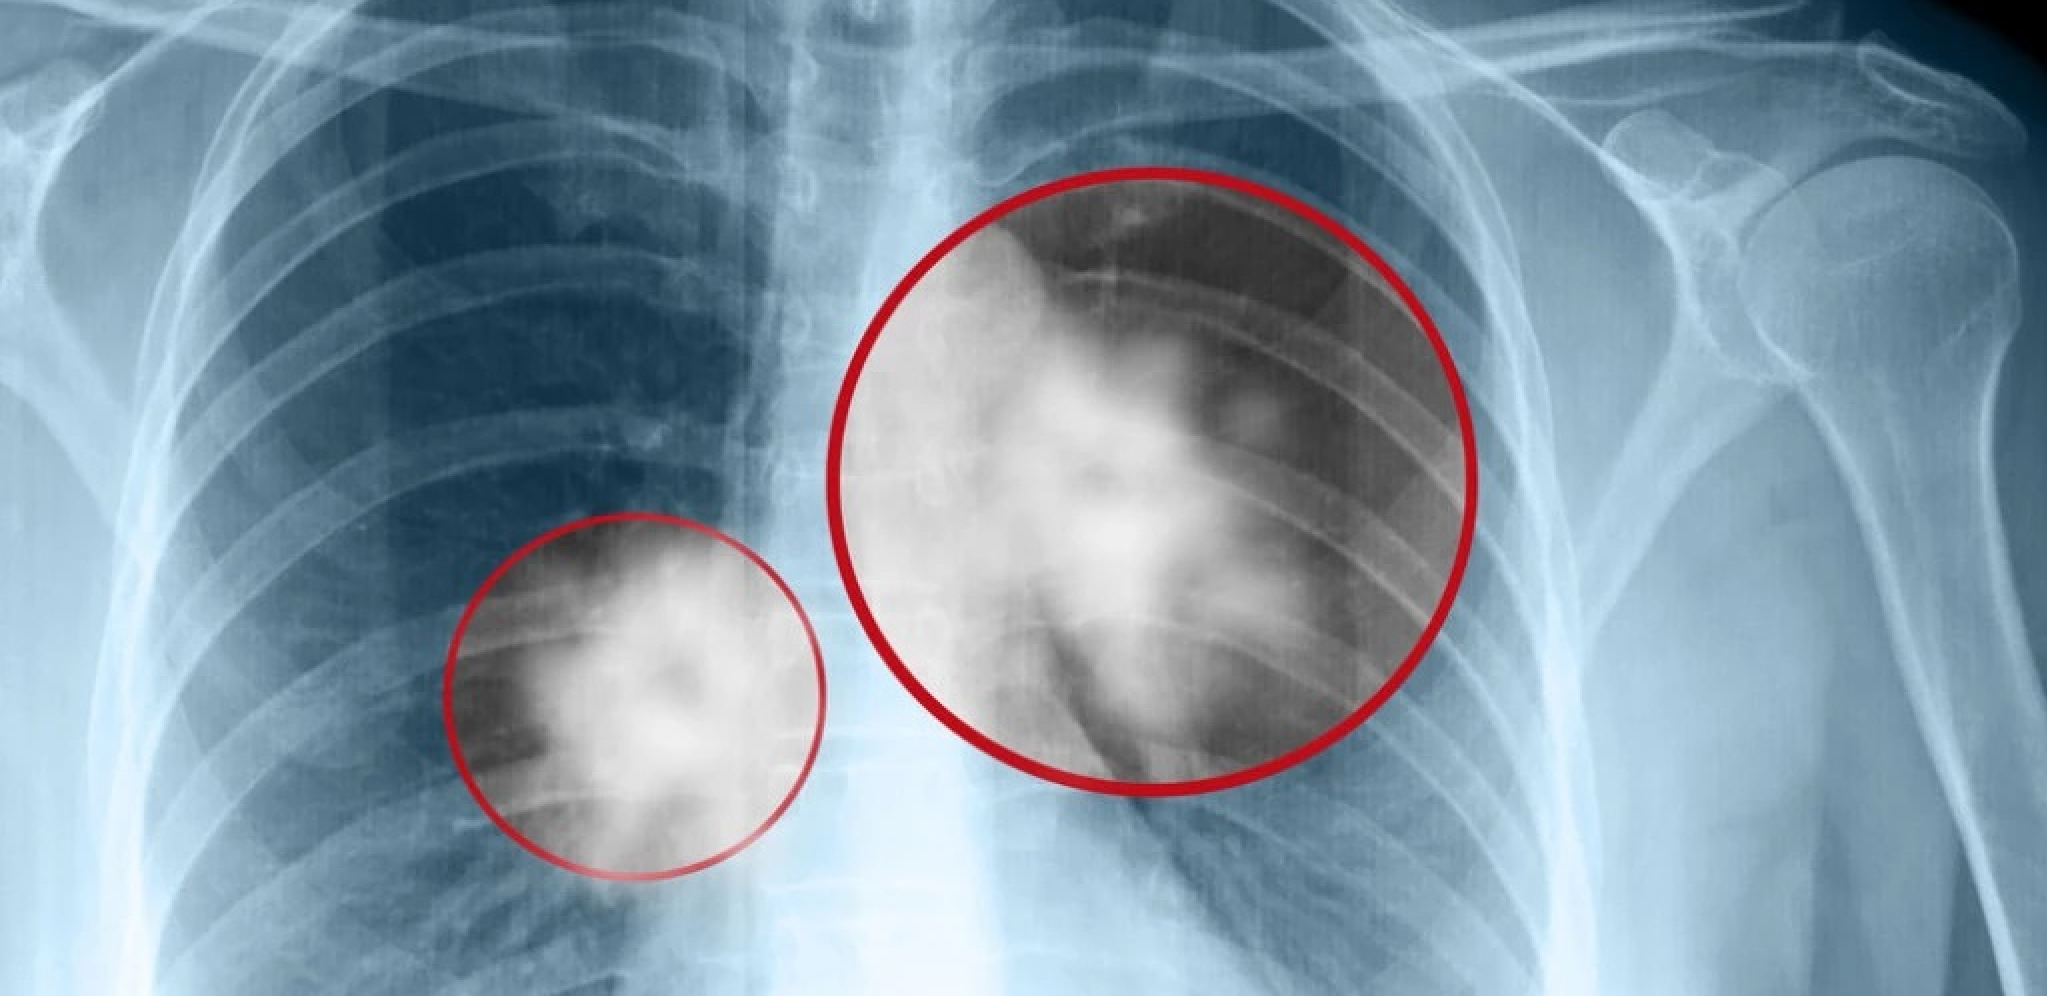

Odavno je poznato da je pušenje direktno povezano sa nastankom karcinoma pluća, od kojeg u našoj zemlji svakodnevno umre 13 osoba. Po tome je Srbija među vodećim zemljama u Evropi. Međutim, uprkos činjenici da su više od 90 odsto obolelih od raka pluća pušači, zabrinjavajuće je da broj onih koji konzumiraju duvan u našoj zemlji stalno raste, a pogotovu među mlađim generacijama. Deca danas počinju da puše već u osnovnoj školi, između 11 i 15 godine.

- Karcinom pluća je podmukla bolest, jer u trenutku kada se osete prvi simptomi većina bolesnika je već u metastatskom stadijumu bolesti. Simptomi u početku mogu da budu vrlo nespecifični - kašalj koji duže traje i ne prolazi na primenu antibiotika, prolongirano febrilno stanje, malaksalost, gubitak apetita, bolovi u grudima. Dodatni problem predstavlja činjenica da većinu bolesnika koji obole od karcinoma pluća predstavljaju pušači koji su već navikli na kašalj i iskašljavanje i to ih zavara. Ne primete kada kašalj postane uporniji, izraženiji i promeni intenzitet. Upravo u tom periodu često se izgubi dragoceno vreme, bolest uznapreduje, terapijske mogućnosti se smanje, a prognoza bolesti postane značajno lošija – objasnio je Ass. dr Mihailo Stjepanović, direktor Klinike za pulmologiju UKC Srbije.